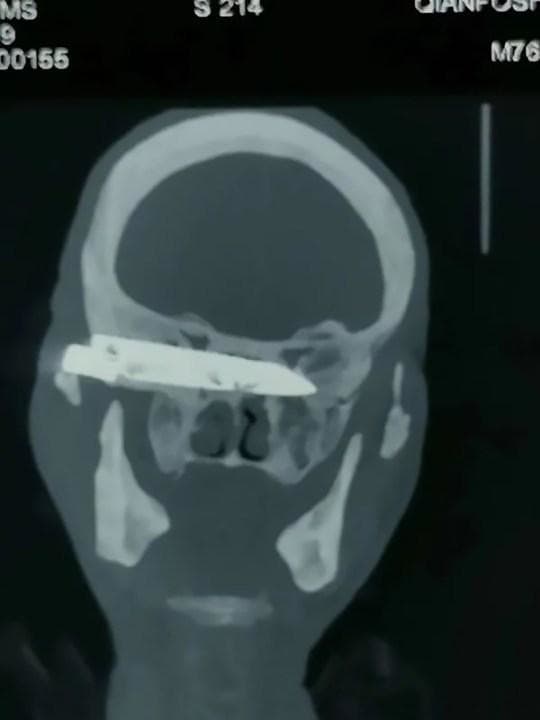

gif_animation 中国にて驚愕のニュース。頭痛、視力障害を訴え病院を受診した70歳男性の頭の中から、「44歳時に強盗に襲われ突き刺されたものの、ずっと放置していたナイフ」が摘出されたとの事。26年ぶりに外に出る事ができたナイフ。一連の画像。[3]images